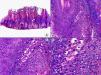

Histopatología de un seudolinfoma desarrollado sobre una lesión de un herpes zóster. A) El epitelio del folículo piloso y la glándula sebácea muestran los cambios citopáticos típicos de infección herpética. B) Abundan los linfocitos atípicos y las figuras de mitosis en el infiltrado alrededor de la lesión. (Hematoxilina-eosina, A x10, B x40, C x200, D x400).